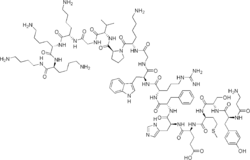

| Formula | C99H155N29O21S |

| Molar mass | 2119.57 g·mol−1 |

Alsactide (INN) (brand name Synchrodyn 1-17 or simply Synchrodyn, former development code name Hoechst 433), also known as alisactide, is a synthetic peptide and analogue of adrenocorticotropic hormone (ACTH) which is used in Italy as a diagnostic agent in kidney function for adrenal insufficiency.[1][2][3] Like ACTH, alsactide is thought to act as a non-selective agonist of the melanocortin receptors, including the ACTH receptor (MC2R). However, it appears to show a different profile of receptor selectivity relative to ACTH, as it apparently demonstrated no evidence of inhibition of endogenous ACTH in Addison's disease patients.[4]